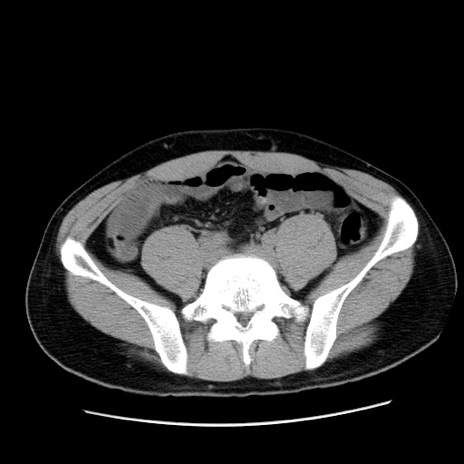

症例36(横断像)

【症例】20歳代 男性

【主訴】心窩部痛

【現病歴】今朝より上腹部痛あり。一旦軽快していたが再度出現したため救急要請。昨日夕に白身の魚を含む刺身を食べた。

【身体所見】BP 136/89mmHg、HR 74/min、BT 37.0℃、腹部:膨満、軟、心窩部に圧痛あり。反跳痛なし、筋性防御なし、腸雑音やや亢進あり。

【データ】WBC 17700、CRP 0.48